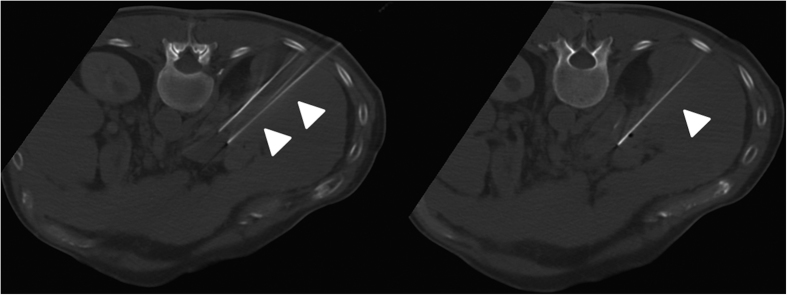

All interventions were performed under general anesthesia and mechanical ventilation with complete muscle relaxation. The electrodes of the NanoKnife® system (Angiodynamics; Latham, NY, US) were percutaneously inserted into all patients using CT fluoroscopy (CareVision, Somatom 16, Siemens, Erlangen, Germany) (Fig. 3).

Figure 3. Same patient as in Figs 1 and 2 with HCC.

Control CT during irreversible electroporation of HCC mass posterior to the main stem of the portal vein. The intervention required the patient to be placed in prone position in order to insert the 3 electrodes (tips of arrows).